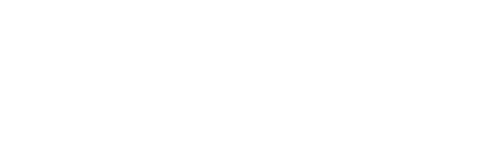

Церебральна мікроангіопатія — це ураження дрібних судин мозку, що живлять його найвразливіші ділянки білої та сірої речовини. Судинні стінки ущільнюються, просвіт звужується, мікроциркуляція слабшає. У тканинах мозку накопичується хронічний брак кисню та поживних речовин. Поступово виникають невеликі ділянки ушкодження, які на знімках МРТ виглядають як світлі плями у білій речовині або як маленькі «дірочки» — наслідки перенесених мікроінсультів. Хвороба розвивається тихо і роками. Але вплив на повсякденне життя може бути значним, бо страждають пам’ять, хода, рівновага, емоції та здатність планувати дії.

Це збірний термін для опису уражень капілярів, артеріол і венул мозку. Коли їхні стінки стають щільними і ламкими, доставка крові у критичні ділянки погіршується. Клітинам бракує кисню, і з’являються мікропошкодження. На МРТ це видно як ділянки зміни сигнала у білій речовині, дрібні порожнини від перенесених лакунарних інфарктів та крихітні крововиливи. Зміни розвиваються повільно, але їхній ефект накопичується. Так формується судинна когнітивна недостатність, порушення ходи, слабкість уваги і швидка втома після розумових навантажень.

Діагноз базується на поєднанні анамнезу, огляду та візуалізації мозку. Лікар оцінює хід, координацію, м’язовий тонус, рефлекси, мову, пам’ять і увагу. Далі призначає МРТ. На зображеннях шукають три основні ознаки: ділянки зміни структури білої речовини навколо шлуночків і у півкулях, дрібні лакунарні інфаркти в базальних ядрах або мосту, а також мікрокрововиливи. Спеціальні режими МРТ підвищують чутливість до цих знахідок і допомагають відрізнити ішемічні плями від інших процесів. Комп’ютерна томографія менш чутлива, але може виявити старі лакуни чи крововилив, якщо МРТ недоступна.